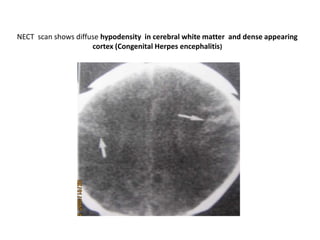

NECT scan shows diffuse hypodensity in cerebral white matter and dense appearing

cortex (Congenital Herpes encephalitis)